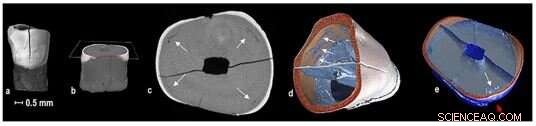

Micro-CT scan shows internal defects in one of the teeth found at the St Mary’s cemetery. Credit: Flinders University

A micro-CT scan shows an external defect in a section of a tooth. Credit: Adelaide Microscopy

Tooth micro-scans taken as part of the PhD investigation at the Adelaide Microscopy. Credit: Flinders University